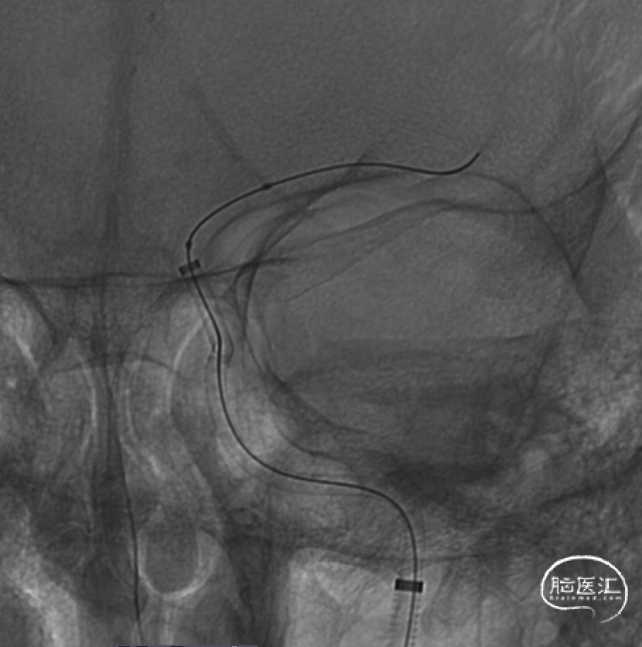

患者仰卧位躺在DSA手术床上,全身麻醉后消毒、铺巾,常规选择股动脉入路,Seldinger法穿刺置入6F 长鞘。用泥鳅导丝及5F 125cm MPA1带领下将长鞘置入左侧颈内动脉起始部,置入通桥银蛇®颅内支持导管 6F 125cm。

通过微导丝带入微导管,微导丝成袢通过血栓段,然后将微导管往远端输送,跨过血栓段,回撤微导管。

白驹®颅内球囊导管 2.0*15mm到位,造影确认。